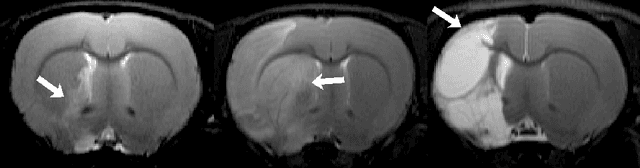

Abstract:Segmentation of rodent brain lesions on magnetic resonance images (MRIs) is a time-consuming task with high inter- and intra-operator variability due to its subjective nature. We present a three-dimensional fully convolutional neural network (ConvNet) named RatLesNetv2 for segmenting rodent brain lesions. We compare its performance with other ConvNets on an unusually large and heterogeneous data set composed by 916 T2-weighted rat brain scans at nine different lesion stages. RatLesNetv2 obtained similar to higher Dice coefficients than the other ConvNets and it produced much more realistic and compact segmentations with notably less holes and lower Hausdorff distance. RatLesNetv2-derived segmentations also exceeded inter-rater agreement Dice coefficients. Additionally, we show that training on disparate ground truths leads to significantly different segmentations, and we study RatLesNetv2 generalization capability when optimizing for training sets of different sizes. RatLesNetv2 is publicly available at https://github.com/jmlipman/RatLesNetv2.

Abstract:Manual segmentation of rodent brain lesions from magnetic resonance images (MRIs) is an arduous, time-consuming and subjective task that is highly important in pre-clinical research. Several automatic methods have been developed for different human brain MRI segmentation, but little research has targeted automatic rodent lesion segmentation. The existing tools for performing automatic lesion segmentation in rodents are constrained by strict assumptions about the data. Deep learning has been successfully used for medical image segmentation. However, there has not been any deep learning approach specifically designed for tackling rodent brain lesion segmentation. In this work, we propose a novel Fully Convolutional Network (FCN), RatLesNet, for the aforementioned task. Our dataset consists of 131 T2-weighted rat brain scans from 4 different studies in which ischemic stroke was induced by transient middle cerebral artery occlusion. We compare our method with two other 3D FCNs originally developed for anatomical segmentation (VoxResNet and 3D-U-Net) with 5-fold cross-validation on a single study and a generalization test, where the training was done on a single study and testing on three remaining studies. The labels generated by our method were quantitatively and qualitatively better than the predictions of the compared methods. The average Dice coefficient achieved in the 5-fold cross-validation experiment with the proposed approach was 0.88, between 3.7% and 38% higher than the compared architectures. The presented architecture also outperformed the other FCNs at generalizing on different studies, achieving the average Dice coefficient of 0.79.